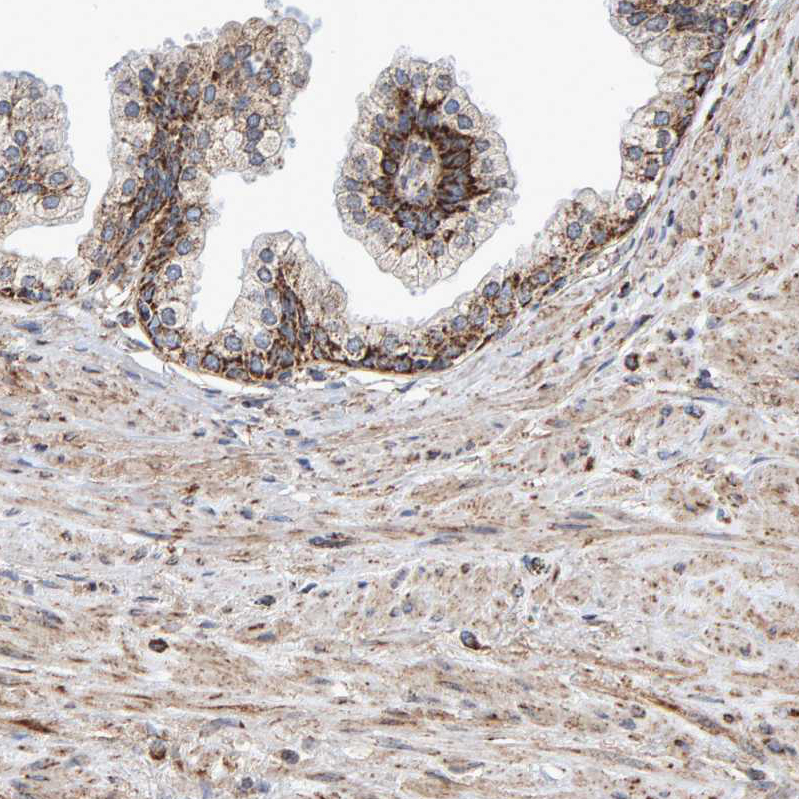

Immunohistochemical staining of human kidney, liver, prostate and small intestine using Anti-MRPL45 antibody HPA023373 (A) shows similar protein distribution across tissues to independent antibody HPA023385 (B).